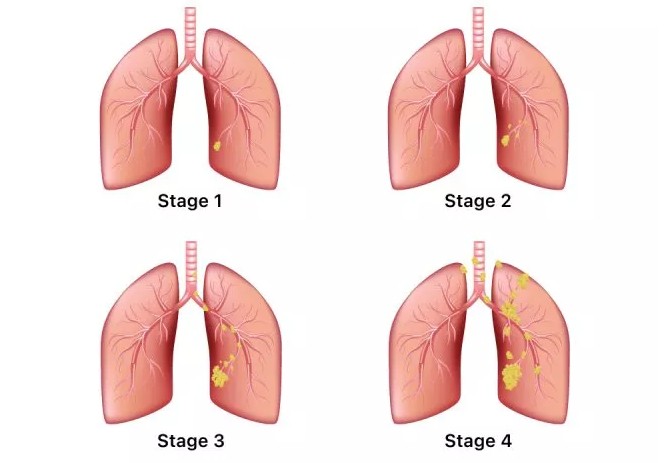

폐암 초기에는 특별한 증상이 없는 경우가 많지만, 암이 진행되면서 다양한 신호를 보낼 수 있습니다. 다음은 폐암 환자들이 흔히 경험하는 10가지 주요 초기 증상입니다.

오늘 함께 알아본 폐암 초기 증상들이 여러분의 건강 관리에 큰 도움이 되었으면 합니다. 폐암은 조기에 발견하면 완치율이 높은 암이므로, 자신의 몸에 나타나는 작은 신호에도 귀 기울이는 습관을 들이는 것이 중요합니다. 오늘 알려드린 내용을 바탕으로 자신의 건강을 체크하고, 궁금한 점이 있다면 언제든지 전문 의료진과 상담하는 것을 잊지 마세요. 우리 모두 건강한 삶을 위해 노력해요!